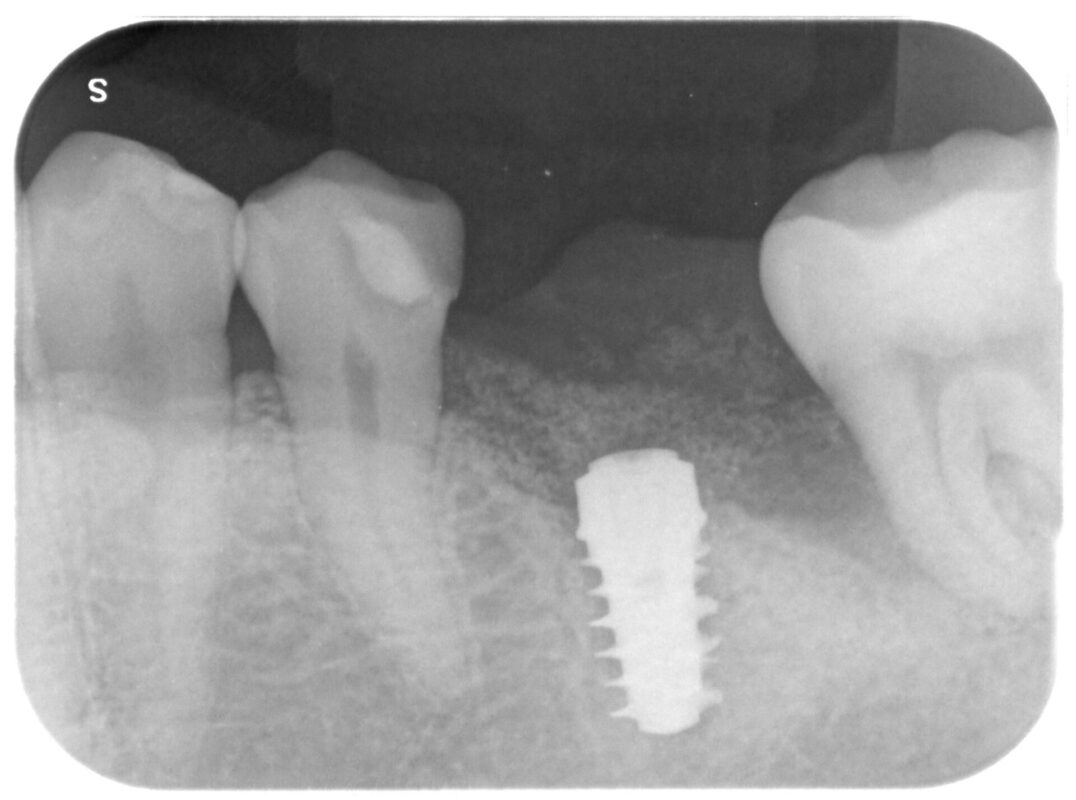

術後4ヶ月

欠損部分にも新製骨が出来つつあります。

昼間時のTCHへの注意、就寝時のマウスピース使用により動揺もほぼ無くなっています。

この後2次オペを経て最終補綴補綴へと治療を進めてゆきます。